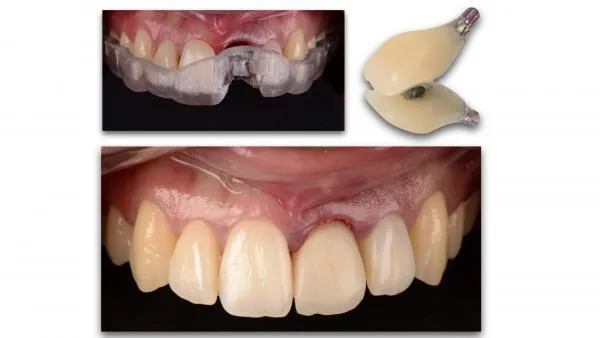

La démocratisation de nouvelles techniques comme le « Digital Smile Design », l’imagerie 3D, les outils de planification implantaire, les guides chirurgicaux stéréolithographiques, les empreintes optiques, la numérisation des modèles et la production par CFAO de piliers et de restaurations anatomiques optimisant nos profils d’émergence, contribuent à assurer la pérennité des restaurations implantaires à long terme.

De même l’amélioration de la prévisibilité des traitements, la mise en place des protocoles et la simplification des procédures cliniques et de laboratoire permettent aujourd’hui l’optimisation du résultat esthétique des restaurations implantaires, plus que jamais fidèles à la notion de « Biomimétisme ».

Le but de cette communication est de présenter une démarche thérapeutique reproductible, de la planification à la conception des restaurations implantaires unitaires et de grandes étendues, qui permet d’anticiper le résultat de nos traitements devenus de plus en plus complexes et de répondre aux principaux objectifs de l’implantologie moderne.